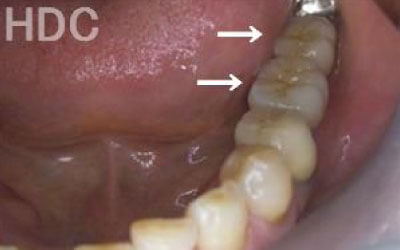

3 歯周病でインプラントが抜けるリスク

細菌(歯垢)の影響で、インプラントを支える歯ぐきや骨が後退することがあります。

つまり、インプラント治療だけでなく、残っている歯の歯周病の検査や治療も非常に重要です。

2 歯が傾いてくる、落ちてくる

歯はお互いに支え合ってバランスを保っています。つまり、歯が抜けるとその支えがなくなり、抜けた部分の隣の歯が傾いたり、上の歯が下にずれてくることがあります。